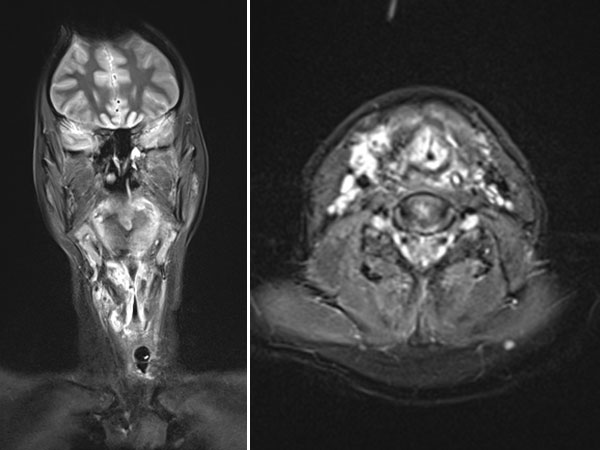

Im Zusammenhang mit einem systemischen Infekt, jetzt weitgehender Verschluss der oberen Atemwege durch eine entzündungsbedingte Zunahme der Schwellung der venösen Malformation, eine Intubation wird notwendig. Es erfolgt eine Biopsie zur Diagnosesicherung. In der MRT in koronarer Schichtführung (T2-gewichtet, fettunterdrückt) ist die Läsion sehr gut sichtbar als stark hyperintense (weiße) Raumforderung. Insbesondere im Hypopharynx und Larynx beidseits ausgedehnte Läsionen.

Auch die MRT zeigt jetzt eine deutliche Besserung. Der Raumforderungseffekt durch die venöse Malformation (hier weiß = stark hyperintens in der koronaren und transversalen, T2-gewichteten, fettunterdrückten MRT) hat abgenommen. Die oberen Luftwege sind zwar noch eng, aber wieder frei zur Spontanatmung.